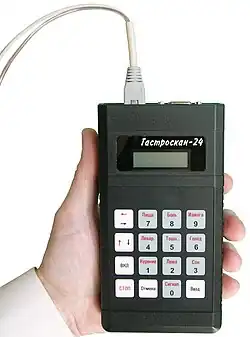

Внутрижелудочная pH-метрия играет важнейшую роль при диагностике и лечении кислотозависимых заболеваний, при исследовании гастроэзофагеальных, дуоденогастральных, фаринголарингеальных рефлюксов. В клинической практике нашли применение несколько методов внутрижелудочной pH-метрии:эндоскопическая (длительность измерений 5 минут), экспресс-pH-метрия (около 30 минут), кратковременная стимулированная (до 2—3 часов) и длительная (24 часа и более) pH-метрия. pH-метрия также применяется для оценки действия кислотоподавляющих препаратов. Измерения выполняется с помощью специальных pH-метрических зондов, вводимых пациенту перорально (при кратковременной pH-метрии), трансназально (при суточной pH-метрии)[21][23], через инструментальный канал эндоскопа (при эндоскопической pH-метрии)[24] или с помощью прикрепляемых к стенке пищевода pH-метрических капсул[25]. Исследование некислых рефлюксов выполняется с помощью импеданс-pH-метрии пищевода[26]. Для дифференциальной диагностики загрудинных болей неясной этиологии применяется гастрокардиомониторинг — одновременное исследование кислотности ЖКТ и электрокардиограммы[21].

Ацидогастромонитор для суточной pH-метрии пищевода и желудка

Ацидогастромонитор для суточной pH-метрии пищевода и желудка 24-х часовая pH-метрия пищевода (фрагмент pH-граммы больного ГЭРБ)